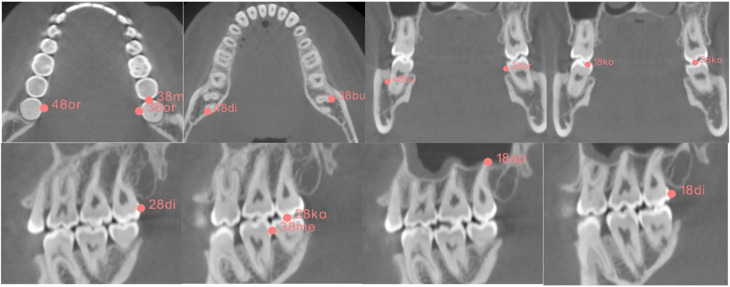

Methods: Three-dimensional CBCT data sets were used to analyze the bilateral positions and dimensions of the wisdom teeth. A total of 215 wisdom teeth from a study population with a mean age of 21 years, including data from 82 male and 58 female patients, were mapped. By transformation into a common coordinate space using the device's chin rest as a joint denominator, the optimal size and location for uni- and bilateral capture of the wisdom teeth were determined, for both best-case and worst-case scenarios with regard to patient positioning.

Results: The minimal FOVs for the lower 3 M capture were H 23.5 mm × R 35.4 mm in the best-case scenario assuming optimal patient positioning and H 35.4 mm × R 36.6 mm in the worst-case scenario with rotational deviation along the transversal axis. For the upper 3 M, the minimal FOVs were H 29.9 mm × R 29.2 mm in the best-case scenario and H 38.6 mm × R 35.6 mm in the worst-case scenario. Unilateral capture of both the upper and lower 3 M required FOV dimensions of H 51.7 mm × R 39.8 mm and H 44.8 mm × R 36.8 mm, respectively. For bilateral capture of all four 3 M, the best-case FOV was H 44.8 mm × R 84.8 mm and the worst-case FOV was H 51.7 mm × R 85.6 mm.